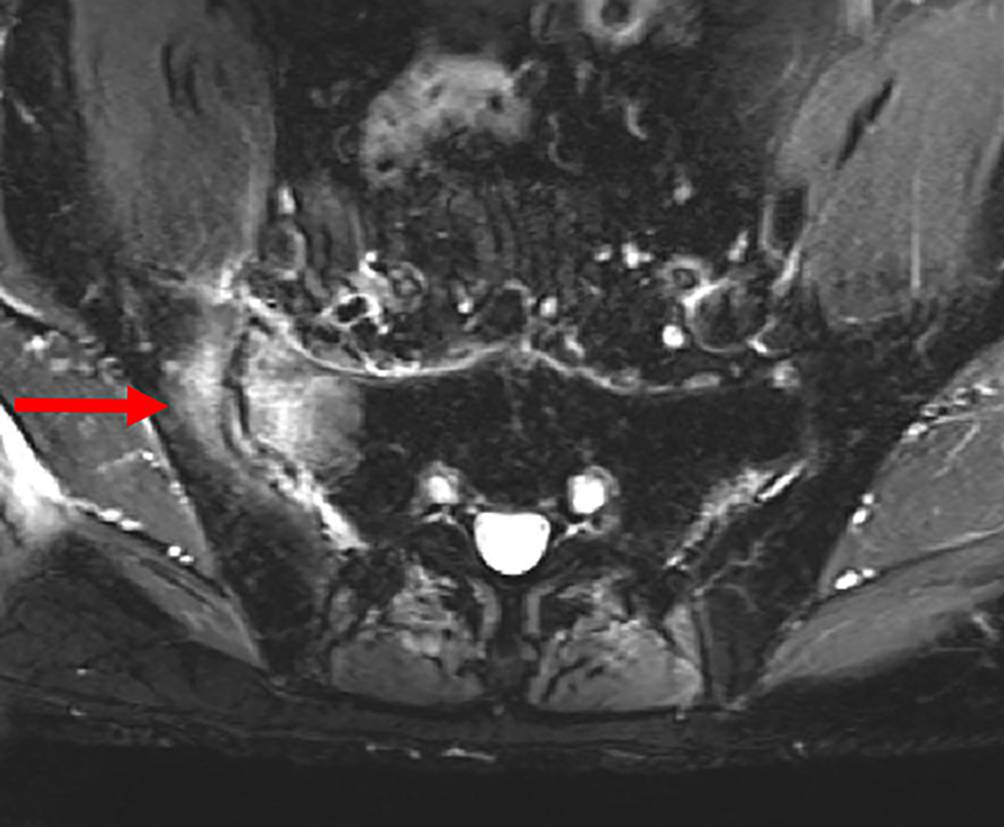

Das KM-Ödem allein ist ein bildgebender Befund, der erst zusammen mit klinischen Symptomen und Befunden als KM-Ödemsyndrom oder Erkrankung angesehen wird [19]. Mit Gelenksschmerz, aber ohne zugrunde liegende Pathologie oder Erkrankung wird es als primäres KM-Ödemsyndrom betrachtet [20], das sekundäre KM-Ödemsyndrom gilt nicht als unabhängige Diagnose. Es tritt dann beispielsweise im Rahmen von Arthrose, Spondyloarthritis (siehe Beispiel in Abb. 1) oder rheumatoider Arthritis, Infektion oder Trauma (siehe Beispiel in Abb. 2) auf [21]. Bis heute gibt es aber zu dieser Unterscheidung keinen internationalen Konsens in der Literatur, mit klarer Definition und Validierung für alle beteiligten Fachdisziplinen.

Abb. 2

Massive posttraumatische Knochenmarksödeme beidseits mit Überschreiten der Medianen bei jungem Patienten ohne typisch entzündlichen Lumbosakralgien (T2-gewichtete Aufnahme). Ebenfalls Ansprechen auf nicht-steroidale Antirheumatika